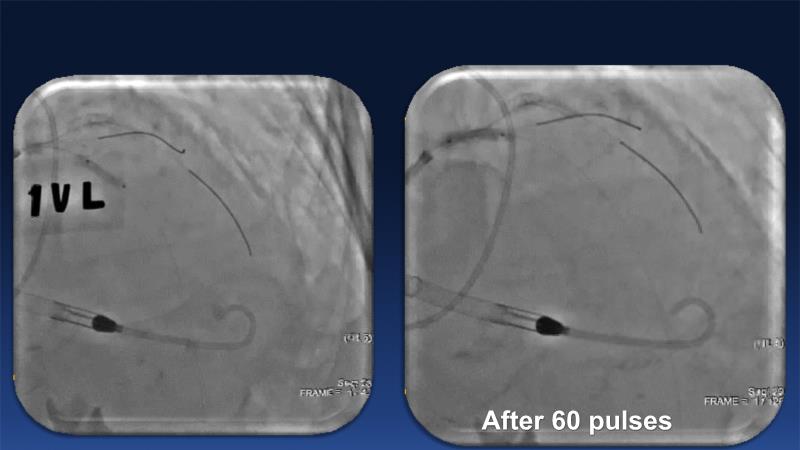

Over the last five years, we have learned that there is a new tool for treating calcium, the greatest enemy of interventional cardiology, which can take various forms: intravascular lithotripsy. In this session, look at how to master this technique in different scenarios, from eccentric calcified lesions to left main bifurcations.

- To understand the mechanism of action of intravascular lithotripsy (IVL) for the treatment of calcified lesions

- To uncover practical tips and techniques for IVL in challenging calcified lesions: eccentric calcified lesions